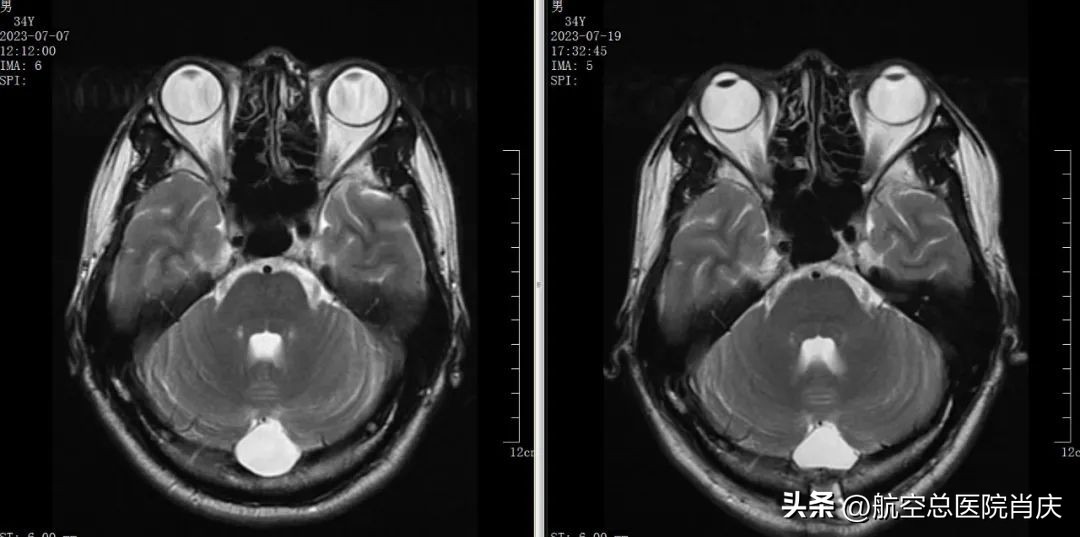

手术前后对比

在最终确定了治疗方案并经过科学周密地准备后,肖庆为患者在全麻下行神经内镜检查术+脑内囊肿开窗造口术+颅骨修补术。手术非常顺利成功,术后头颅CT、MRI检查显示陈先生恢复良好,之前的症状全部消失了,心情也变得明朗起来,夫妻二人的脸上终于露出了笑容。